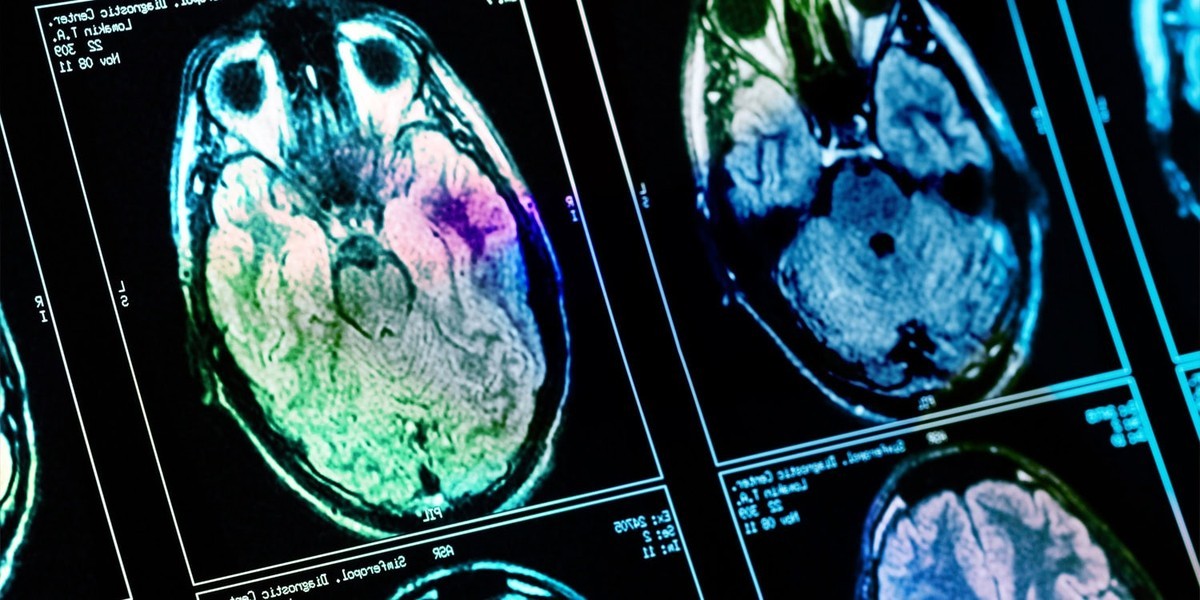

در مورد تاثیر درآمد بر مغز، یه تحلیل روی داده های توموگرافی گسیل پوزیترون در کره نشون داده که درآمد خانوادگی بالاتر با افزایش فعالیت عصبی (که از طریق افزایش متابولیسم گلوکز تخمین زده می شه) در بخش های هسته دم دار، پوتامن، قشر سینگولیت قدامی، هیپوکامپ و آمیگدال مغز مردهای میانسال در ارتباطه. این نواحی مغز توی پردازش پاداش و تنظیم استرس نقش دارن. این مقاله در European Journal of Neuroscience.

در این بخش تصویری شماتیک از بررسی های آزمایشگاهی روی ساختار عصبی نمایش داده شده است که به درک بهتر موضوع کمک می کند.

این تصویر نشان دهنده اهمیت ابزارهای تصویربرداری در شناسایی تفاوت های عملکردی مغز بر اساس متغیرهای اجتماعی و اقتصادی است.

نتایج نشون داد افرادی که درآمد خانوادگی بالاتری داشتن، معمولا سطح تحصیلات شون هم بالاتر بود. همچنین درآمد خانوادگی بالاتر با افزایش متابولیسم گلوکز در نواحی هسته دم دار، پوتامن، قشر سینگولیت قدامی، هیپوکامپ و آمیگدال مغز همراه بود. این یافته ها به وضوح ارتباط مستقیم و مثبت بین درآمد بالا و فعالیت مغزی را نشان می دهند و بر تاثیر درآمد بر مغز تاکید می کنند.

این یعنی فعالیت عصبی در این نواحی در افرادی که درآمد خانوادگی بالاتری داشتن، بیشتر بوده. این مناطق مغز در پردازش پاداش و تنظیم استرس نقش دارن. جالبه که سطح تحصیلات با الگوهای فعالیت مغزی ارتباطی نداشت.

نویسندگان مطالعه این طور نتیجه گیری کردن که درآمد خانواده با افزایش متابولیسم گلوکز مغز در نواحی درگیر در پردازش پاداش مرتبطه. این تحقیق بینش های مهمی درباره تاثیر درآمد بر مغز ارائه می دهد، هرچند نیاز به مطالعات بیشتر در این زمینه است.

Wealthier men show higher metabolism in brain regions controlling reward and stress